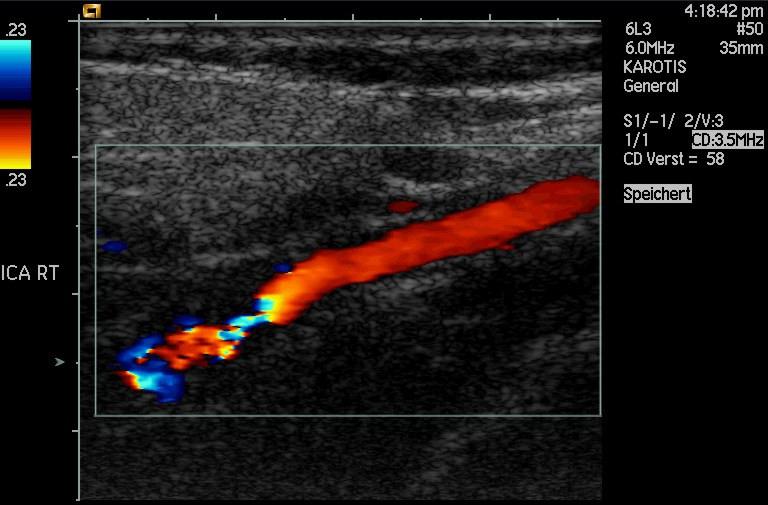

How much detail can ultrasound reveal? The image in Figure 17.47 is typical of low-cost systems, but that in Figure 17.48 shows the remarkable detail possible with more advanced systems, including 3D imaging. Ultrasound today is commonly used in prenatal care. Such imaging can be used to see if the fetus is developing at a normal rate, and help in the determination of serious problems early in the pregnancy. Ultrasound is also in wide use to image the chambers of the heart and the flow of blood within the beating heart, using the Doppler effect (echocardiology).

Another major use of ultrasound in medical diagnostics is to detect motion and determine velocity through the Doppler shift of an echo, known as Doppler-shifted ultrasound. This technique is used to monitor fetal heartbeat, measure blood velocity, and detect occlusions in blood vessels, for example. (See Figure 17.49.) The magnitude of the Doppler shift in an echo is directly proportional to the velocity of whatever reflects the sound. Because an echo is involved, there is actually a double shift. The first occurs because the reflector (say a fetal heart) is a moving observer and receives a Doppler-shifted frequency. The reflector then acts as a moving source, producing a second Doppler shift.

A clever technique is used to measure the Doppler shift in an echo. The frequency of the echoed sound is superimposed on the broadcast frequency, producing beats. The beat frequency is and so it is directly proportional to the Doppler shift () and, hence, the reflector’s velocity. The advantage in this technique is that the Doppler shift is small because the reflector’s velocity is small, so that great accuracy would be needed to measure the shift directly. But measuring the beat frequency is easy, and it is not affected if the broadcast frequency varies somewhat. Furthermore, the beat frequency is in the audible range and can be amplified for audio feedback to the medical observer.